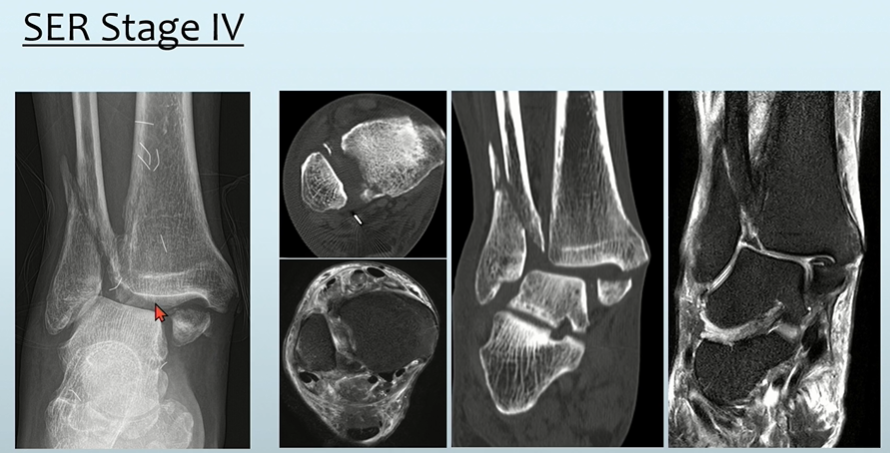

Stage3에 합당한 소견을 보이면서, MM 골절이 동반되어 있으므로 Stage4로 판단할 수 있습니다.